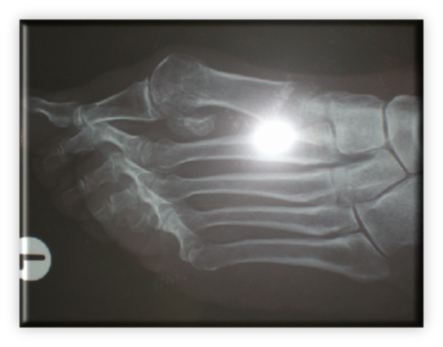

Πρόκειται για σύνθετη παθολογία του μεγάλου δακτύλου του ποδιού, που εκτός από την παραμόρφωση σε βλαισσότητα, όπως το όνομα υποδηλώνει, συνυπάρχει στροφική παραμόρφωση και γενικότερα παραμόρφωση ολόκληρου του πρώτου στοίχου (ταρσός, μετατάρσιο, δάκτυλο) αλλά και των μικρότερων δακτύλων. Πιο συγκεκριμένα, υπάρχουν οστεόφυτα στις αρθρώσεις και κυρίως στην έσω επιφάνεια της κεφαλής του πρώτου μεταταρσίου (κότσι), τροφικές αλλοιώσεις του δέρματος και δερματικοί κάλοι στα σημεία αυξημένης φόρτισης, λέπτυνση του υποδορίου λίπους στην πελματιαία επιφάνεια, εξάρθρημα σησαμοειδών οσταρίων, ανισορροπία στους άξονες έλξης των τενόντων περί του μεγάλου δακτύλου, υμενίτιδα στην έσω επιφάνεια της μεταταρσιοφαλλαγγικής η οποία είναι και πολύ επίπονη. Εμβιομηχανικά ο άξονας φόρτισης του ποδιού μεταφέρεται στο διάστημα μεταξύ πρώτου και δεύτερου στοίχου με αποτέλεσμα το πρώτο μετατάρσιο να δέχεται λιγότερα φορτία από όσο θα έπρεπε και τελικώς μεταταρσιαλγία στις κεφαλές των μικρότερων μεταταρσίων, παραμορφώσεις των μικρότερων δακτύλων με συχνότερη αυτή του δευτέρου που καταλήγει σε γαμψοδακτυλία, εφίππευση επί του πρώτου, στεόφυτα και δερματικό κάλο στην ραχιαία επιφάνεια της πρώτης φαλαγγοφαλαγγικής άρθρωσης, οστεοχόνδρινες αλλοιώσεις των αρθρώσεων και τελικά αρθρίτιδα.

ΒΛΑΙΣΟΣ ΜΕΓΑΛΟΣ ΔΑΚΤΥΛΟΣ (HALLUX VALGUS)

Στις ακτινογραφίες πρέπει να μετρηθούν η γωνία μεταξύ 1ου και 2ου μεταταρσίων με ανώτερα όρια 8-9 μοίρες, η γωνία βλαισσότητας του 1ου μεταταρσίου και 1ης φάλαγγας που όταν ξεπερνά τις 15 μοίρες ορίζεται παθολογική. Συμπληρωματικά μπορούν να μετρηθούν οι γωνίες προσανατολισμού της αρθρικής επιφάνειας κεφαλής 1ου μεταταρσίου και η γωνία προσανατολισμού κεντρικής αρθρικής επιφάνειας 1ης φάλαγγας του μεγάλου δακτύλου.